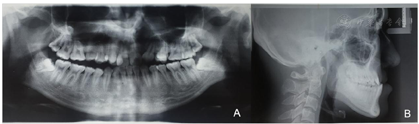

曲面断层片检查(图3-A):B1、B3间骨量不足,牙根远中倾斜,第三磨牙阻生。

头颅侧位片检查(图3-B)表1:ANB-4.5,骨性三类反合。